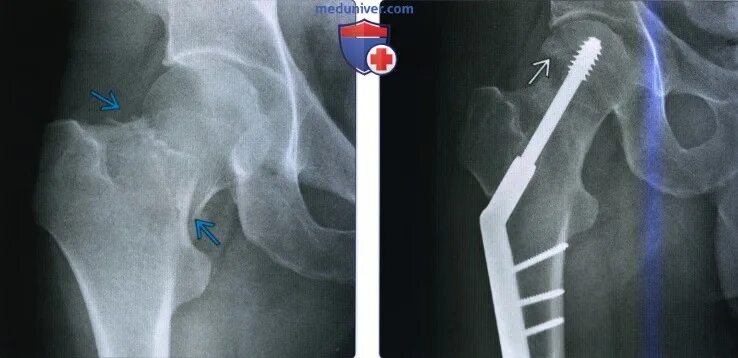

Перелом шейки бедра мкб 10 у взрослых